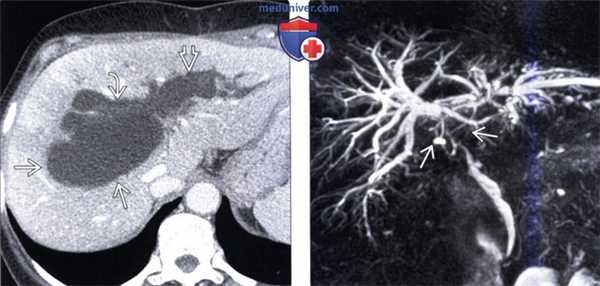

(Слева) На корональной КТ с контрастным усилением (MIP-реконструкция) у пациента, которому была выполнена трансплантация печени, определяются признаки окклюзии печеночной артерии с внезапным ее «обрывом» В возле места отхождения от чревного ствола.

(Справа) На рентгенограмме (холангиография) у этого же пациента определяются признаки ишемической холангиопатии, обусловленной окклюзией печеночной артерии, в т.ч. доминирующая стриктура общего протока, а также иррегулярность внутрипеченочных протоков. (Слева) При ЭРХПГ у пациента с желтухой после трансплантации печени определяется дефект наполнения желчного протока на уровне ворот печени, обусловленный плотной желчью; внутрипеченочные желчные протоки диффузно неравномерны. Несмотря на то, что при УЗИ признаков непроходимости печеночной артерии не выявлено, у пациента возникли тромбоз воротной вены и отторжение трансплантата.